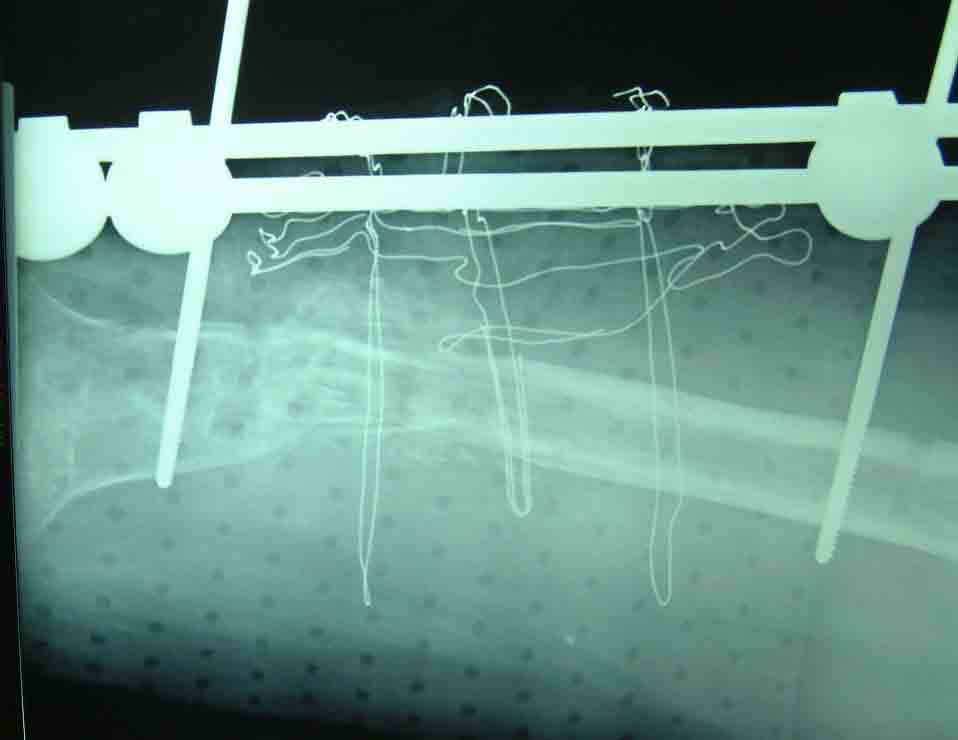

X 线片显示左股骨中下1/3骨折区大段骨缺损,大约缺损6CM ,骨质疏松,断端变尖。外固定架子已经松动失效。

大段的骨缺损修复前

采用短缩的方法,将断端互相接触,植自体骨,

术后X

术后注射红骨髓和BMP